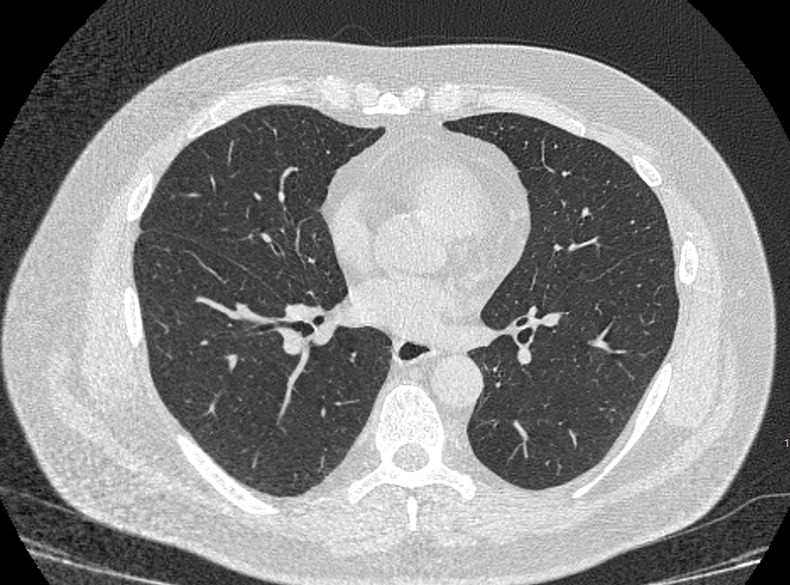

Во время исследования рентгеновская трубка томографа вращается вокруг исследуемой области и производит множество послойных снимков с шагом 0,5-1 мм. Полученные снимки поперечного сечения с помощью компьютерной программы могут быть преобразованы в 3D-изображения исследуемого органа или участка ткани. Это позволяет выявлять практически все заболевания легких на ранних стадиях и назначать своевременное лечение.

В медицинском центре «Доступная медицина» используется современный 128-срезовый компьютерный томограф TOSHIBA AQUILION CXL, на котором проводится сканирование легочной ткани. За счет увеличенного количества детекторов аппарат производит снимки с большой скоростью и минимальной дозой облучения. При этом инновационные цифровые приложения позволяют получить объемные изображения легочной ткани высокой четкости, контрастности и в мельчайших подробностях.